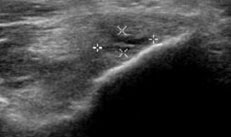

Suggest X-ray and ultrasound

Choosing the right hand Therapist starts with them being able to read your X-rays and then fabricate the right brace for you. The therapists at Action Rehab are experienced in assessing and reading X-rays.